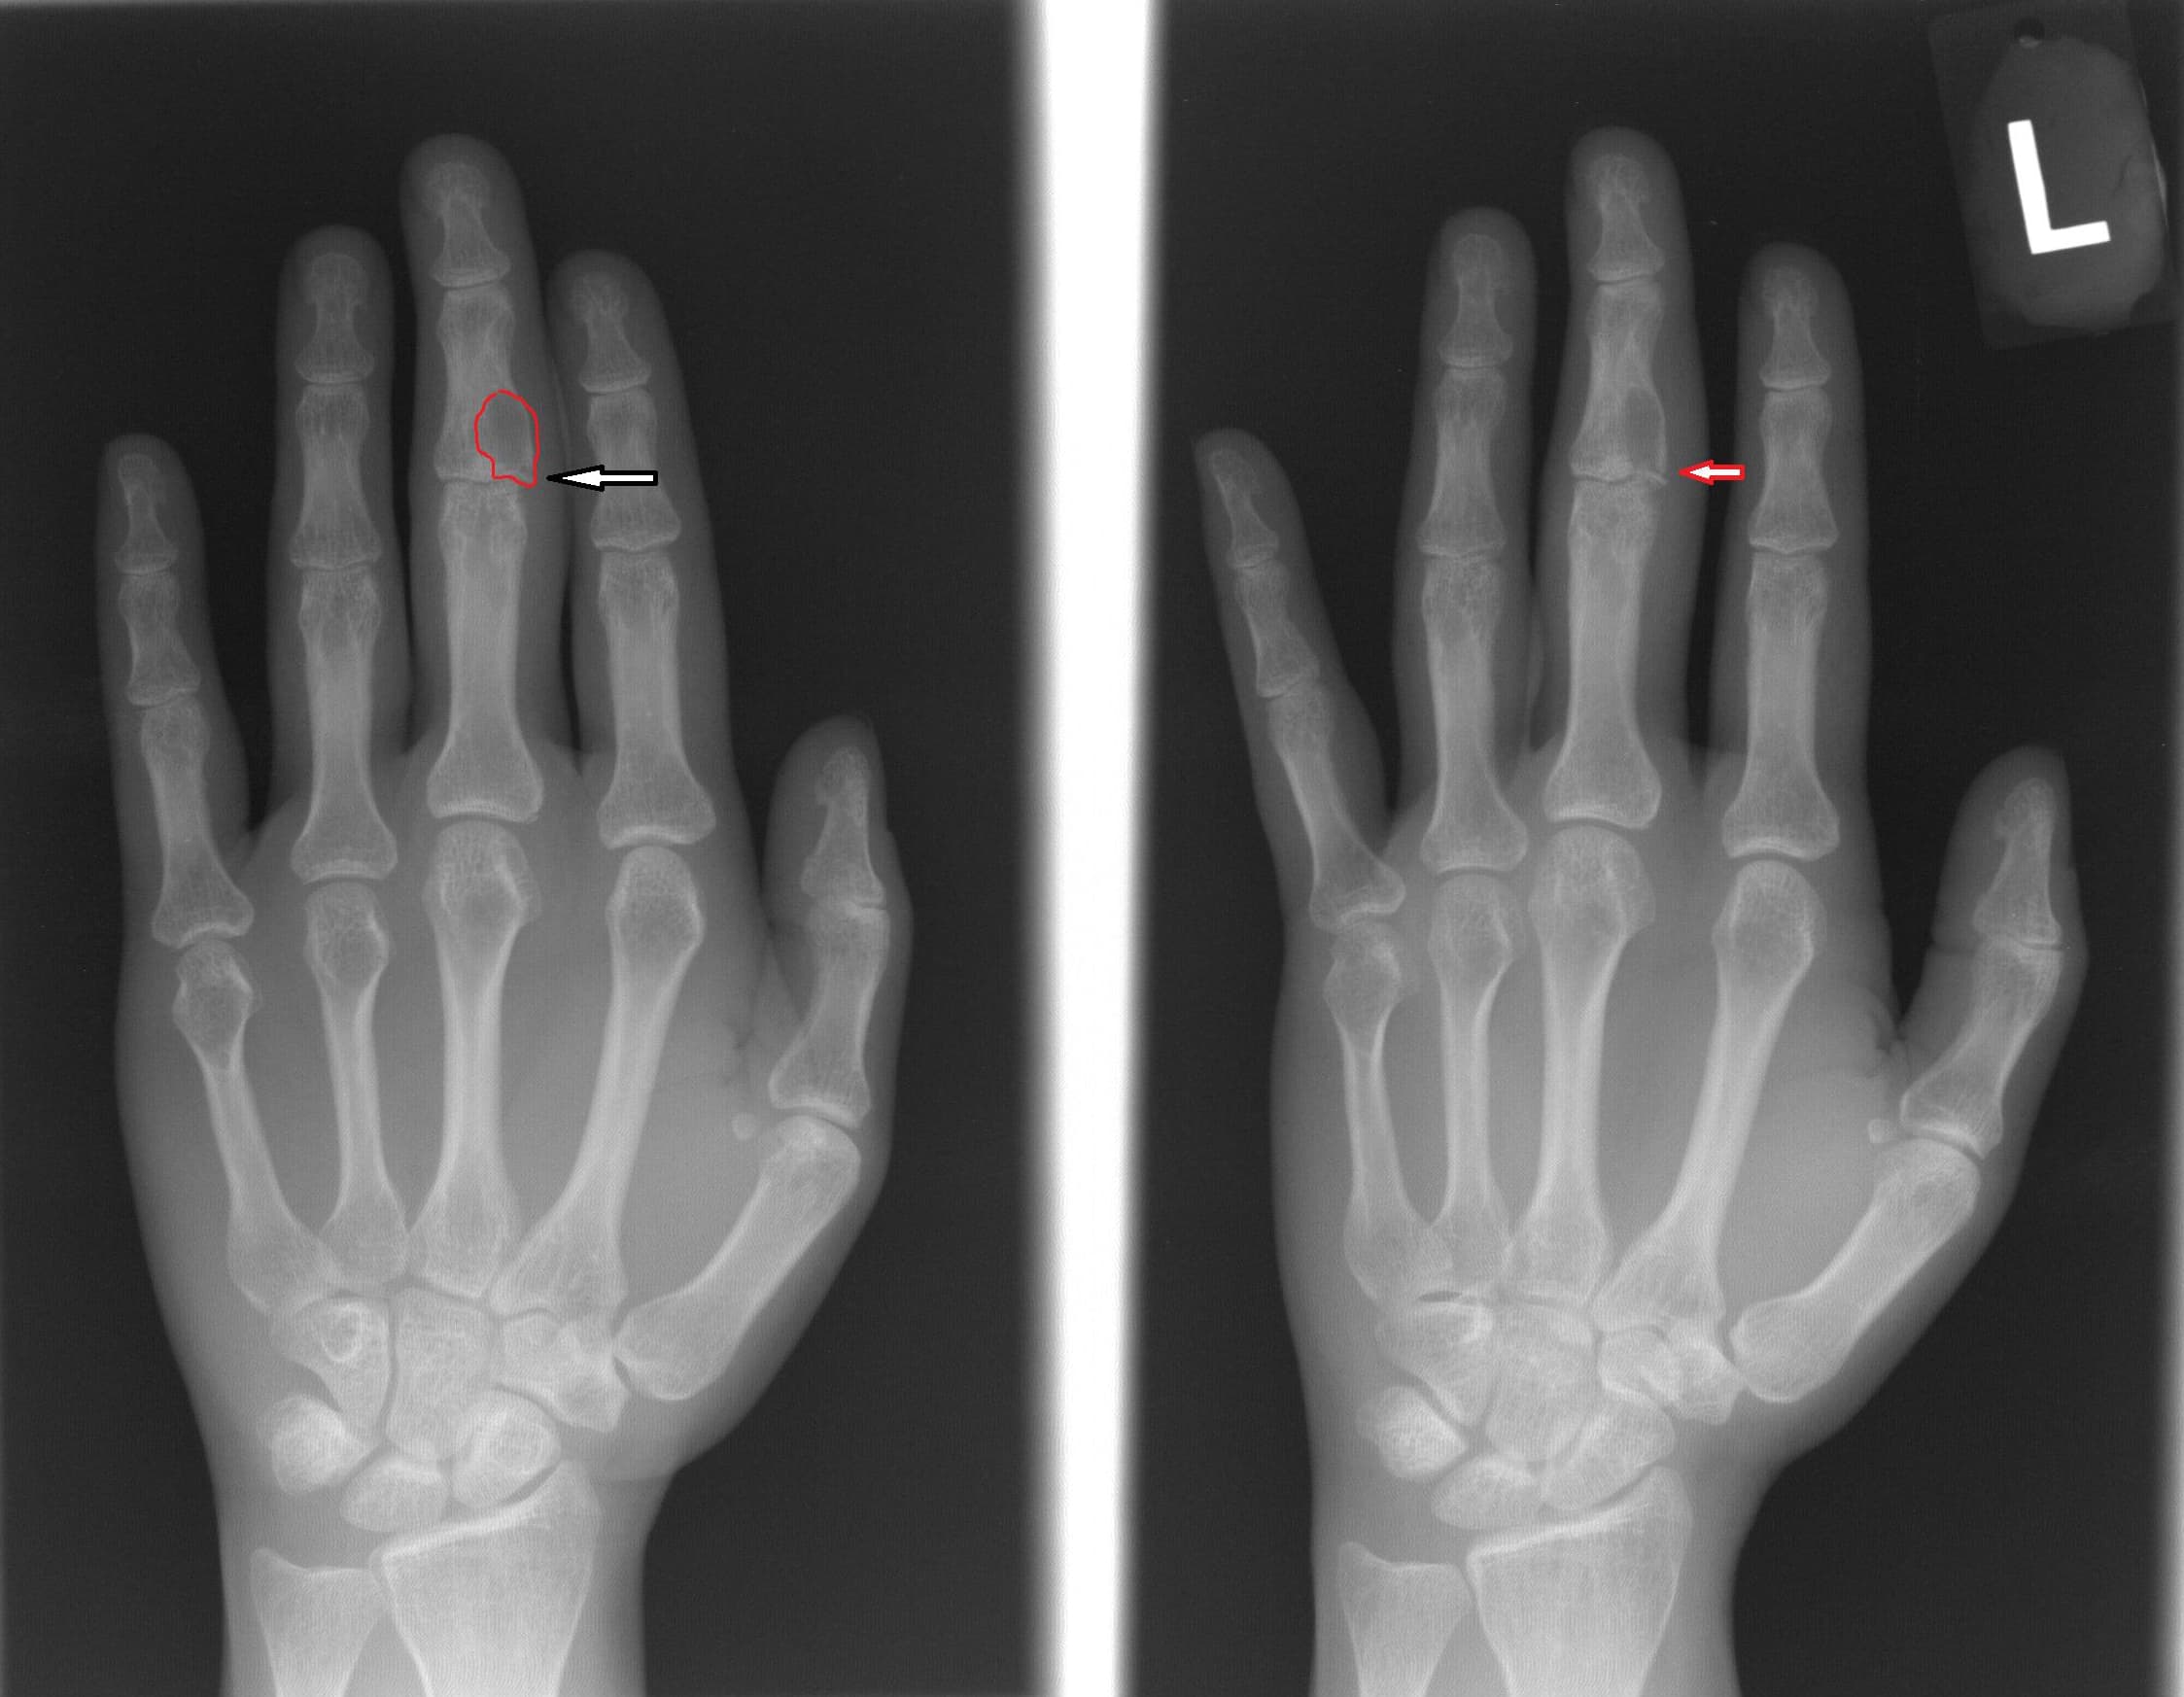

Figure 1 from Pathogenesis of finger joint lesions in rheumatoid

Figure 1 from Pathogenesis of finger joint lesions in rheumatoid Finger Joint Lesions Distal interphalangeal (dip) joint injuries involve the terminal extensor tendon (mallet finger) and flexor digitorum profundus tendon (jersey finger). Swollen finger joints are frequently the result of inflammation caused by an infection, injury, or disease. Finger joint pain can affect a person’s everyday activities and may have several causes. It is common for swelling and stiffness to accompany finger joint. Finger Joint Lesions.